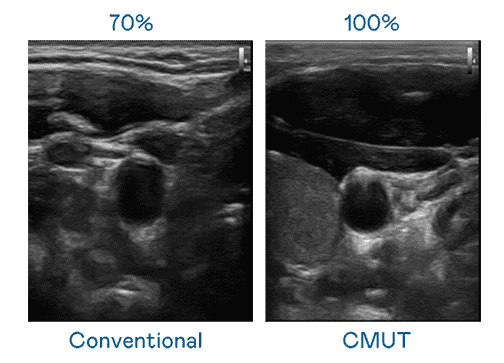

CMUT 技术是一种用电容式微机电元件来产生超音波讯号的技术。。与传统 PZT 压电式技术相比,,,CMUT 频宽增加 30%,,,,更宽频的超音波讯号让影像解析度大幅提升,,,是实现高影像品质医疗超音波扫描、、促进精准医疗发展的关键技术。。

大频宽带来超清晰影像

超音波影像的解析度高低,,,,首先取决于探头能发出的讯号频宽。。。。壹号平台 CMUT 可提供高清晰的超音波讯号,,,,提供高频宽、、、、高灵敏度、、、、影像纹理细节更高的超音波影像,,,,协助医护人员缩短影像判读时间及利用精准的医疗影像进行诊断。。。